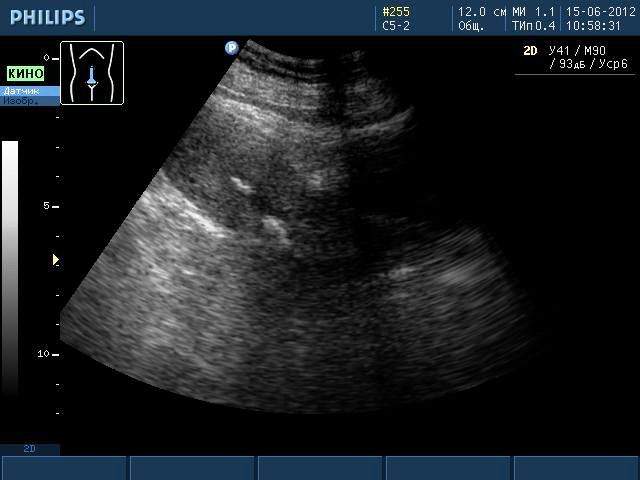

Такие образования хорошо видны при ультразвуковом исследовании, МРТ. Но во время УЗИ не видны ткани, из которых состоит образование, поэтому о наличии кальцината можно только предположить. Такая ситуация требует дополнительного обследования женщины, чтобы исключить заболевания гораздо серьезнее, чем наличие отложений солей кальция.

Кальцинат на УЗИ

Распространенным методом диагностики является ультразвуковое исследование детородного органа. Гинекологи предлагают трансабдоминальное УЗИ, которое позволяет исследовать патологии органа с помощью датчиков, которые врач водит по животу пациентки.